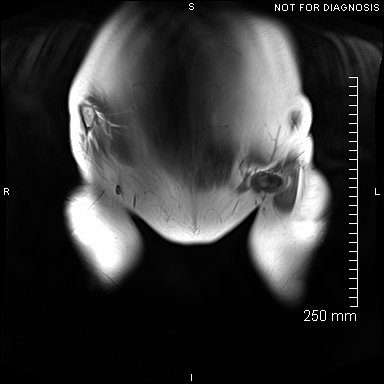

Coronal MRI showing left sided gluteal muscle wasting but no signs of loosening. There were no other abnormalities.

EOS scanning (low radiation dose, 3D scanning in functional positions of standing and sitting) was used to assess leg lengths whilst standing and pelvic tilt whilst sitting.

EOS scanning taken 4-months after the operation. Zara was able to fully weight bear, she was trendelenburg negative and her EOS revealed no LLD. She had no pain in the joint and was using an exercise bike and swimming for rehabilitation.